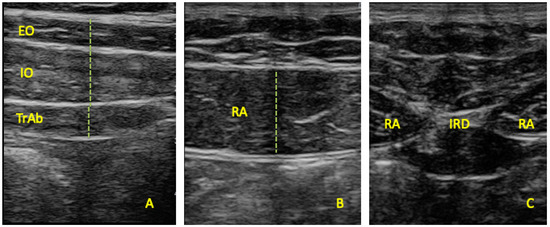

2.3. Outcome Measurements

Figure 1. Ultrasound thickness assessments of the (A) EO, IO, TrAb, (B) RA, and (C) IRD.